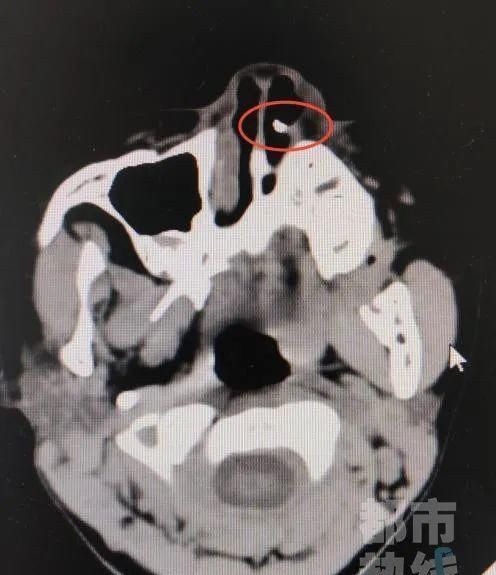

近日,西安市第三医院接诊了一位6岁女童患者。孩子的鼻腔不适,通气不好。为孩子进行仔细查体后,医生发现在她的左侧鼻腔底部有一白色凸起,触之质硬。检查后所有人都惊呆了CT片子上显示在孩子的左侧鼻腔里竟然有一个白色高密度异物影一颗牙

鼻子里怎么会长牙女童的妈妈仔细回忆想起来这可能是三年前丢的那颗门牙